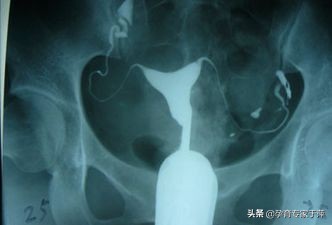

输卵管造影就是将造影剂注射到子宫腔内,造影剂可以经过输卵管进入盆腹腔内,在X线下可以清晰地看到子宫腔及两侧的输卵管的形态,是否通畅,是堵塞、黏连还是通而不畅,病灶的位置等都能清晰的看到。子宫输卵管造影术是输卵管通畅度的一线筛查手段。

患者做完造影后都是需要医生来根据造影片子来解读输卵管的通畅性的,虽然这属于比较专业的范畴,但在这里我也给大家列举几个典型的片子给大家一些参考。

1、输卵管通畅

可以看到一侧或双侧输卵管伞端有造影剂溢出,盆腔有造影剂涂抹。